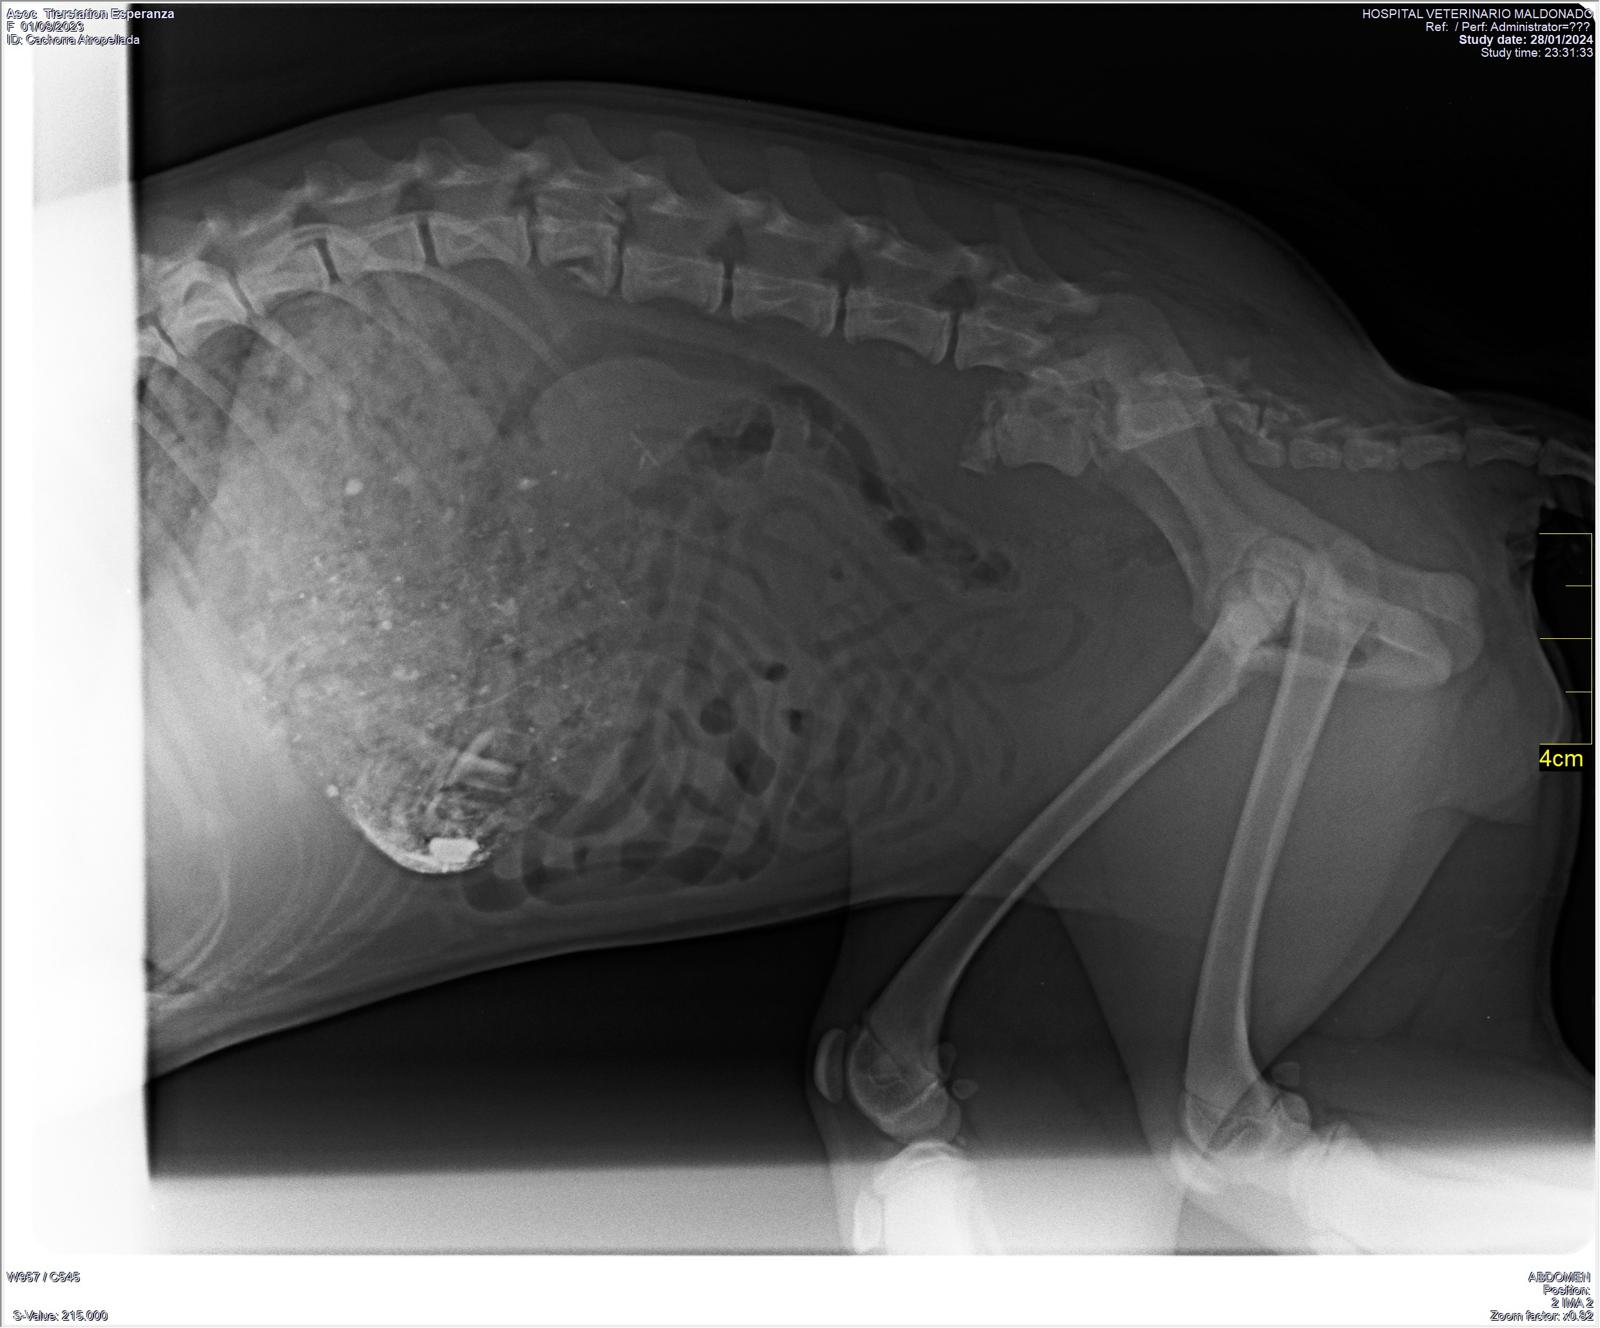

Als Eva Chula in der Klinik besuchen wollte sah sie auf der Autobahn dieses kleine Wesen, das von einem Auto massiv erfasst worden war. Schnell war das ca 5,5 Monate alte Welpchen eingepackt und liegt nun in derselben Klinik wie Chula. Es muss einen massiven Schlag auf den Kopf bekommen haben und auch die Hinterbeine sind betroffen. Es muss geröntgt werden, noch wissen wir nicht, ob es überlebt…

29.1.24: Leider sind die Resultate ernüchternd! Das Kleine hat vermutlich das Rückgrat gebrochen und da sind keine guten Prognosen…

30.1.24: Von aussen kann man die Situation nicht richtig beurteilen. Der Spezialist sagt, man müsse bei einer Operation entscheiden in welche Richtung es geht. Wenn er sieht, dass die Kleine eine Chance hat wird er operieren, wenn er während der Operation das Gegenteil sieht, wird er ihrem Leiden ein Ende setzen müssen. Heute Nachmittag wird sie operiert…

3.2.24: Mila geniesst das Futter sehr. Als sie geröntgt wurde sah man im Magen ganz viele Steine. Aus Hunger muss sie Steine gegessen haben….